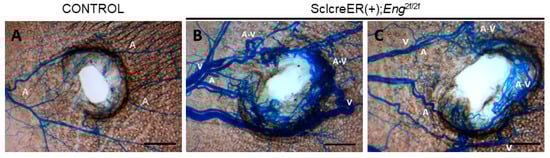

3.1. Endothelial Cell Eng Gene Deletion Induced BAVM Development